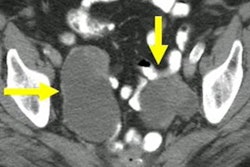

Philpott and colleagues explored whether such surveillance could demonstrate high sensitivity for asymptomatic disease and earlier-stage detection, as well as whether it could be cost-effective. For the study, they used Abcodia's Risk of Ovarian Cancer Algorithm (ROCA) test, a tool that calculates the probability of a woman having epithelial ovarian or fallopian tube cancer with an algorithm that analyzes the rate of change in tumor markers.

The study included 767 women. Of these, BRCA variant status was confirmed in 755 (99%), with BRCA1 variants in 339, BRCA2 in 410, and both in six. Eight ovarian cancers were identified, and out of these, two were occult at RRSO (both stage 1a) and six were screen-detected.